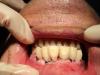

Evgen-Vozhd Опубликовано 24 июня, 2013 Поделиться Опубликовано 24 июня, 2013 (изменено) Полностью согласен с Олегом.Временные - только винтовая.И фиксация надежней, и риск попадания цемента отсутствует и снимать легче.Позвольте узнать, данная конструкция в лабе делалась методом нанесения или в кадкаме? В каком виде техник получил ориентиры для окклюзионной плоскости? делался ли предварительно силиконовый ключ. Целесообразно ли сразу ввинчивать угловые винтовые платформы в таких случаях для последующего их использования для постоянной конструкции? Изменено 24 июня, 2013 пользователем Evgen-Vozhd Ссылка на комментарий

ossa-rr Опубликовано 24 июня, 2013 Поделиться Опубликовано 24 июня, 2013 Позвольте узнать, данная конструкция в лабе делалась методом нанесения или в кадкаме? В каком виде техник получил ориентиры для окклюзионной плоскости? делался ли предварительно силиконовый ключ. Целесообразно ли сразу ввинчивать угловые винтовые платформы в таких случаях для последующего их использования для постоянной конструкции?Тоже любопытна технология изготовления данного протеза. Похоже на гарнитурные зубы на бизисе из акриловой пластмассы. Поправьте, если не так. Ссылка на комментарий